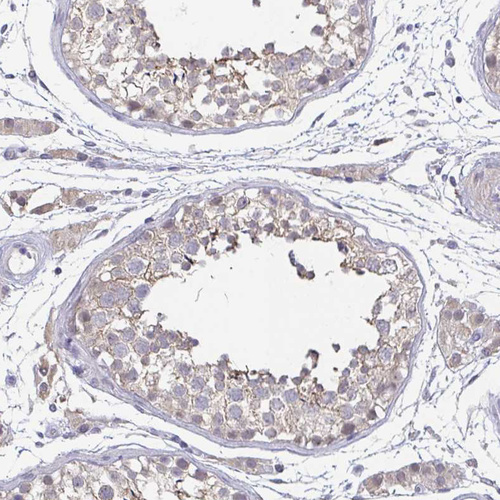

Immunohistochemistry analysis in human cerebral cortex and liver tissues using HPA061615 antibody. Corresponding NEFH RNA-seq data are presented for the same tissues.